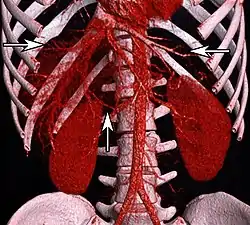

Volume rendering of an abdominal CT, with hepatic veins annotated by arrows. The aorta and branches is seen in center. | |